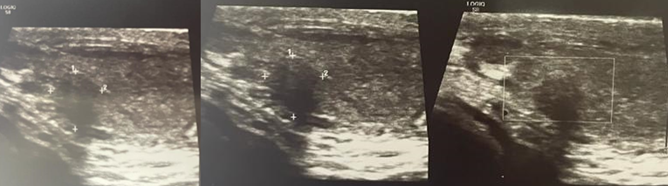

Por el dolor crónico y el aumento de consistencia del testículo izquierdo, se realiza ecografía testicular, en la que se evidencia lesión heterogénea de 2 cm de diámetro máximo, dependiente de polo inferior de testículo izquierdo; sin otros hallazgos de importancia ( Figura 1).

Se decide su programación para realizar orquiectomía radical izquierda, la cual se realiza sin complicaciones, con hallazgos de cordón espermático libre de neoplasia, piel de escroto libre de neoplasia, teniendo como reporte histopatológico: tumor de células de sertoli testicular, con bordes quirúrgicos libres de neoplasia, cordón libre de neoplasia, epidídimo libre de neoplasia, con bordes quirúrgicos negativos, con descripción microscópica en la que se observa: neoplasia intratesticular circunscrita compuesta por células cuboidales con atipia leve y citoplasma pálido que conforman estructuras tubulares y cordones sobre un estroma extensamente colagenizado que compone más de la mitad de la neoplasia. (Figura 1-2, 3-4). Cursando con evolución satisfactoria, con cicatrización completa de la herida, y actualmente en vigilancia, sin necesidad de tratamiento adyuvante.

Los datos publicados en 2016, provenientes de la base de datos nacional de cáncer de EE.UU., mostraron que sólo el 0,4% de los pacientes, fueron diagnosticados con tumores de células de Sertoli o células de Leydig malignos 18. De estos pacientes solo 65 (21%) de estos pacientes tenían un tumor maligno de células de Sertoli. En este estudio la tasa de supervivencia general a 1 y 5 años, para los tumores de células de Sertoli en estadio I fue: 93% (IC del 95% (intervalo de confianza): 83-100) y 77% (IC del 95%: 62-95), respectivamente. Estos tumores de Sertoli generalmente se encuentran de manera casual, como lesiones escrotales indoloras, sin la presencia de ningún otro síntoma, u ocasionalmente dolor leve. De los estudios que se disponen la ecografía testicular es la más útil, en este estudio un tumor de células de Sertoli se observa, como una lesión intratesticular hipoecoica, que de manera cotidiana suele ser solitaria 1 9. El tratamiento de estos tumores es la orquiectomía radical; se necesitaría tratamiento adicional solo si la cirugía no fue radical o si durante los estudios de extensión se documenta metástasis a distancia.